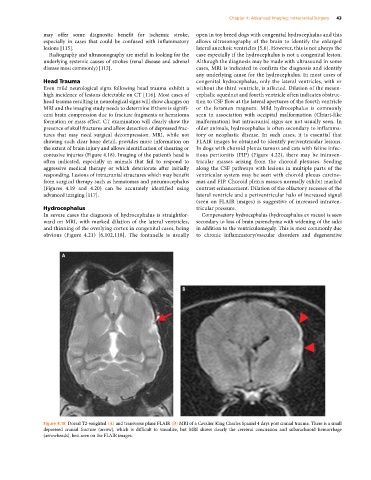

Figure 4.18 Dorsal T2‐weighted (A) and transverse plane FLAIR (B) MRI of a Cavalier King Charles Spaniel 4 days post cranial trauma. There is a small

depressed cranial fracture (arrow), which is difficult to visualize, but MRI shows clearly the cerebral concussion and subarachnoid hemorrhage

(arrowheads), best seen on the FLAIR images.